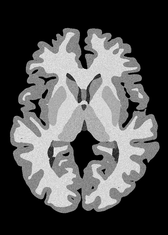

4.2 Registration to a 100 micron ex-vivo brain MRI volume

To showcase the efficacy of our method on real large scale images, we register a 250 in-vivo MRI image (Lüsebrink et al., 2017) to a 100 ex-vivo FLASH human brain volume (Edlow et al., 2019). This represents an inverse problem with more than 11.2B optimizable parameters (compared to 20M for clinical datasets), or 44.8GB of GPU memory. The entire problem does not fit on most GPUs, necessitating distributed multimodal registration. We optimize a composite transform - affine followed by a diffeomorphic mapping; details can be found in Section E.1. Multimodal deformable registration took 58 seconds on 8 NVIDIA A6000 GPUs, which is unprecedented at this resolution. Fig. 6 shows qualitative results, highlighting the ability to register highly detailed structures such as cerebellar white matter; these structures are not visible at macroscopic scales. The resultant advantages of performing registration at this scale can allow researchers to characterize the neuroanatomy at microscopic resolutions and allow morphometric analysis of cortical layers and subcortical nuclei among other structures.